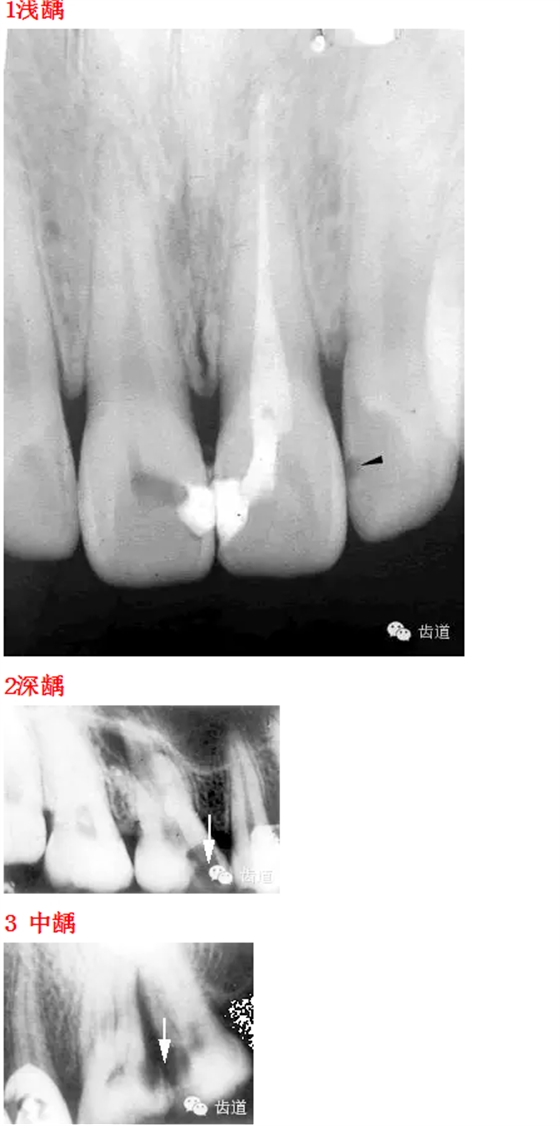

26種口腔病變X光片